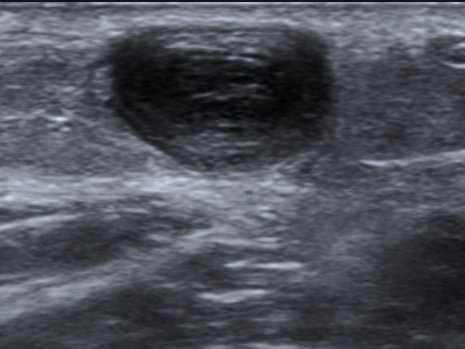

🟢 Test : Compression transversale

-

Appui perpendiculaire progressif

La veine normale s’écrase totalement

Si non compressible → TVP jusqu'à preuve du contraire

🧪 Signes directs de thrombose

Veine non compressible ± douleur à la compression

Visualisation d'un thrombus intraluminal

Absence de flux Doppler

Veine dilatée par rapport à l’artère